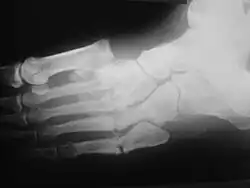

Radiologic findings

First, it is important to recognize that two types of abnormality may be detected. One is termed atrophic, in which there is osteolysis of the distal metatarsals in the forefoot. The more common form of destruction is hypertrophic joint disease, characterized by acute peri-articular fracture and joint dislocation. According to Yochum and Rowe, the "6 D's" of hypertrophy are:

- Distended joint

- Density increase

- Debris production

- Dislocation

- Disorganization

- Destruction

The natural history of the joint destruction process has a classification scheme of its own, offered by Eichenholtz decades ago:

Stage 0: Clinically, there is joint edema, but radiographs are negative. A bone scan may be positive before a radiograph is, making it a sensitive but not very specific modality.

Stage 1: Osseous fragmentation with joint dislocation seen on radiograph ("acute Charcot").

Stage 2: Decreased local edema, with coalescence of fragments and absorption of fine bone debris.

Stage 3: No local edema, with consolidation and remodeling (albeit deformed) of fracture fragments. The foot is now stable.

Atrophic features:

- "Licked candy stick" appearance, commonly seen at the distal aspect of the metatarsals

- Diabetic osteolysis

- Bone resorption